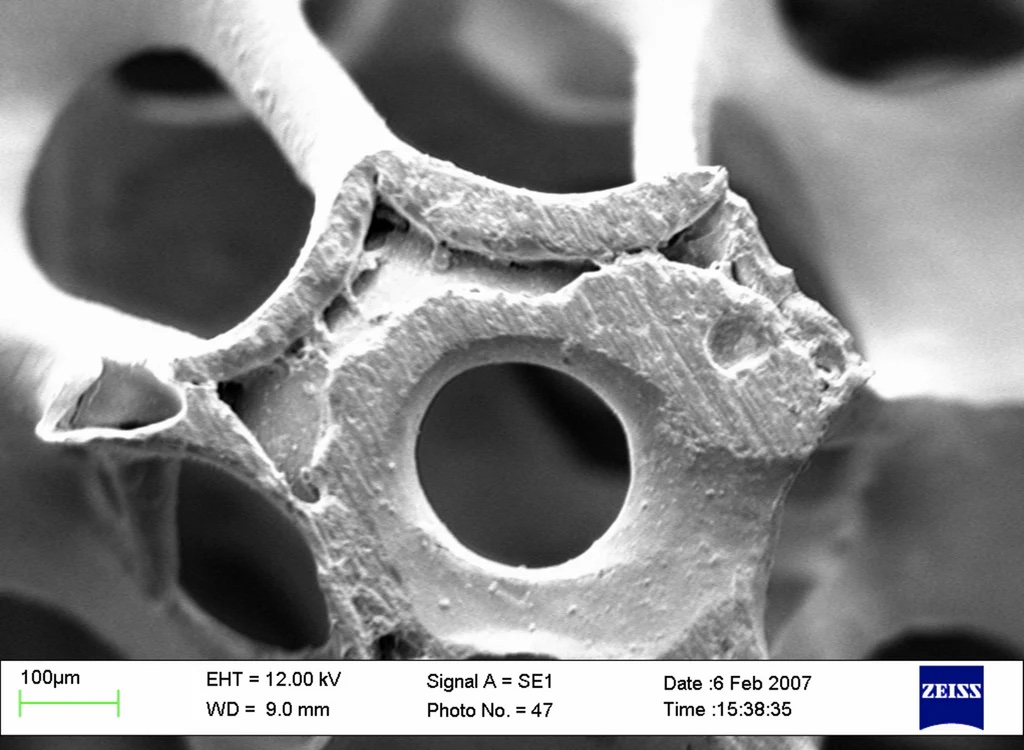

One of the more significant limitations of current synthetic bone grafts is insufficient cell migration into implanted bone grafts. In some cases, there is limited surface area for cell attachment, and in others, there is an insufficient supply of oxygen and nutrients for the frontage cell-line. Other products may be slow in increasing cell numbers inside the bone graft or may have a limited amount of blood vessel formation and blood circulation that assuages healthy cell growth. It is also not uncommon in cases of bone grafting for there to be slower or fewer cell differentiation. In all, these limitations correlate to the end result of poor bone regeneration and, in some cases, non-union between the new growth and the pre-existing bone.

First and foremost, the dental bone graft should provide a suitable substrate such that it is both biocompatible and osteoconductive. While all bone grafts are osteoconductive to an extent, the degree in which healthy bone growth is observed varies between products. It is also important that an implant has high biocompatibility as bone grafts would ideally be integrated into the patient’s system naturally over a period of time.

In the same vein of thought of new bone growth, it is vital that implanted bone grafts are capable of providing mechanical integrity and nutrient support during the process of bone regeneration. A preemptive collapse of the graft could disrupt the healing process, and a lack of nutrients to migrating cells prevents healthy cell growth and the formation of capillaries and blood vessels. On a cellular level, the product should allow for ease of migration of cells, abundant surface for cell to anchor proper distribution, proliferation, and microenvironments for osteogenesis and angiogenesis. Additionally, bone grafts should be customizable to the specific needs of the patient undergoing a dental procedure or surgery and therefore more widely applicable to a variety of cases. OsteoGeneTM Tech strove to meet the criteria for an ideal synthetic bone graft with InRoad® spearheading the movement to more efficient alloplast products that overcome the limitations commonly seen for bone regeneration. InRoad®’s design meets all the qualifications to be considered an ideal bone graft and actually goes beyond simply meeting the minimum requirements. With its three-part structure, InRoad® has a superior sucking property compared to the top bone grafts available on the market today, which facilitates greater ease in cell migration and new bone growth at the site of application, and has no reported adverse effects during its testing period. At this current point in time, InRoad® is opening a new stage for bone grafts for both medical practitioners and patients alike.